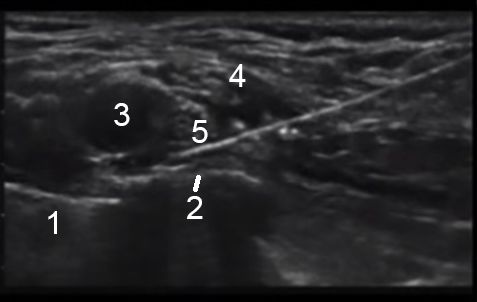

Supraclavicular Ultrasound Labeled 2 Image

Lung

Rib

Artery

Brachial Plexus

Needle